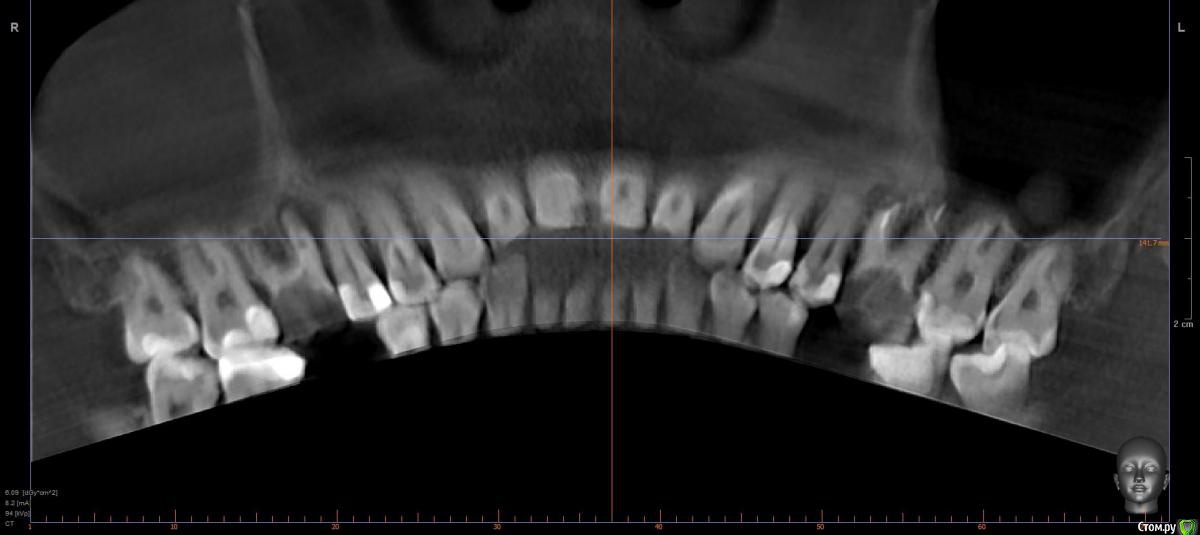

Faramir Опубликовано 18 апреля, 2019 Поделиться Опубликовано 18 апреля, 2019 (изменено) Здравствуйте.Подскажите пожалуйста, возможно ли лечение верхних шестерок и нижней семерки для устранения очагов воспаления?Правая шестерка в течении месяца два раза болела с образованием болезненного валика на десне над ним но после полосканий проходила. Над левой шестеркой больше полугода свищ над которым изредка надувается и лопается белый шарик. Зубы лечились около 15 лет назад. До этого года не беспокоили. Шестерки с помощью установки в каналы/канал стекловолоконных штифтов и приклеивания на них отдельно изготовленной накладки/коронки. Семерка лечилась путем обычного заполнения каналов и последующего пломбирования. Изменено 18 апреля, 2019 пользователем Faramir Ссылка на комментарий

krokomot Опубликовано 18 апреля, 2019 Поделиться Опубликовано 18 апреля, 2019 Удалять! шестёрки, седьмой снизу нужно еще покрутить кт и сделать прицельный снимок. 2 Ссылка на комментарий

krokomot Опубликовано 18 апреля, 2019 Поделиться Опубликовано 18 апреля, 2019 Я не разбираюсь. Просто хотелось бы аргументированных ответов и прогнозов.Прочитайте правила форума, мы не проводим обучение пациентов, и что бы вы начали разбираться вам нужно много изучить, оценив вашу ситуацию, я вам ответил на ваш вопрос, верхние шестерки не подлежат лечению не потому что их каналы можно перелечить, а потому, что слишком мало тканей осталось у зубов, зубы разрушены слишком значительно и лечение каналов проводится в подходящих для дальнейшего протезирования зубах, моё мнение удалять. 2 Ссылка на комментарий

suballex Опубликовано 19 апреля, 2019 Поделиться Опубликовано 19 апреля, 2019 Обучать конечно не надо, но привести пару веских аргументов считаю каждый доктор имеет возможность. Пациенту от этого легче принять решение. Иначе образуется информационный вакуум в котором можно пойти по ложному пути. В любом случае спасибо за ваш ответ.После проведения всех манипуляций, от зубов ничего не останется. Прогноз их восстановления не благоприятный. Это раз.Вероятность успеха повторного эндодонтического лечения не более 50%, для зубов, которые гораздо менее сложные, чем ваши. Это два.Аргументов достаточно? 1 Ссылка на комментарий

dentikl Опубликовано 19 апреля, 2019 Поделиться Опубликовано 19 апреля, 2019 каждый доктор имеет возможность. Пациенту от этого легче принять решение. ситуация для очной консультации.по снимкам-шансов 0 Ссылка на комментарий

red_butler Опубликовано 23 апреля, 2019 Поделиться Опубликовано 23 апреля, 2019 Объём оставшихся твёрдых тканей не позволяет прогнозируемо восстановить зубы+1 удалять Ссылка на комментарий